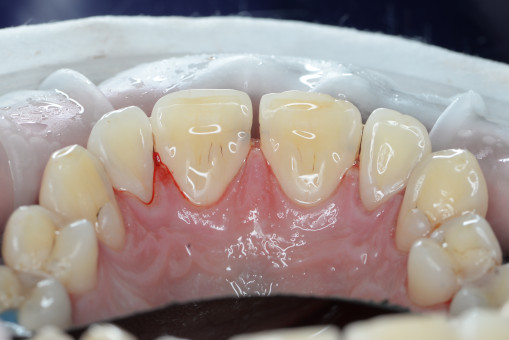

А прежде, чем вы посмотрите фотографии «до» и «после» лечения слизистой оболочки полости рта, проведенных в нашей клинике, хочу поблагодарить большое количество наших пациентов, которые поверили, прониклись нашей концепцией, и мы вместе, именно вместе победили болезни десны, гингивит и пародонтит!

До/после лечения